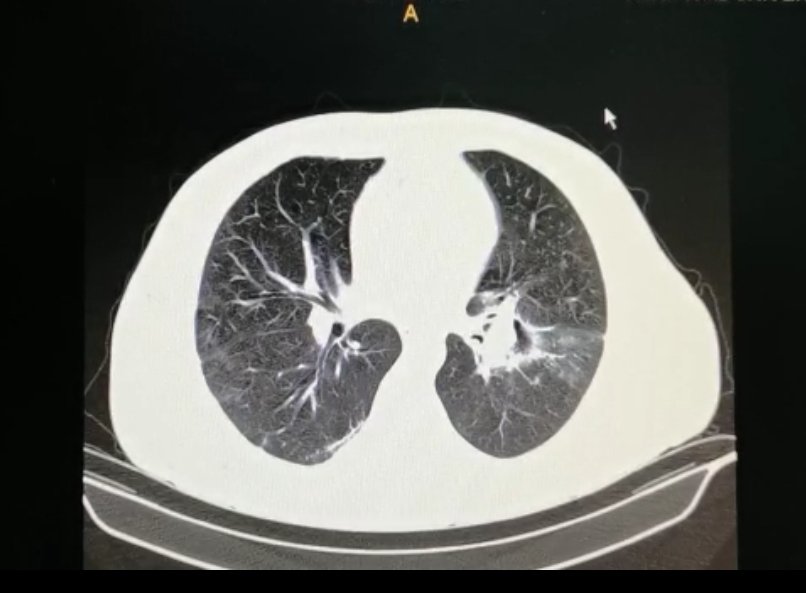

Aspergilosis pulmonar invasiva en paciente neutropenico

Aspergilosis pulmonar invasiva en paciente neutropenico from www.scielo.org.bo